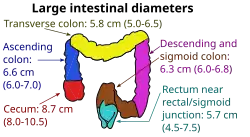

| Diameter | Assessment |

|---|---|

| <2.5 cm | Non-dilated |

| 2.5-2.9 cm | Mildly dilated |

| 3-4 cm | Moderately dilated |

| >4 cm | Severely dilated |

Radiological signs of bowel obstruction include bowel distension (small bowel loops dilated >3 cm) and the presence of multiple (more than 2) air-fluid levels on supine and erect abdominal radiographs.[16] Ultrasounds may be as useful as CT scanning to make the diagnosis.[17]